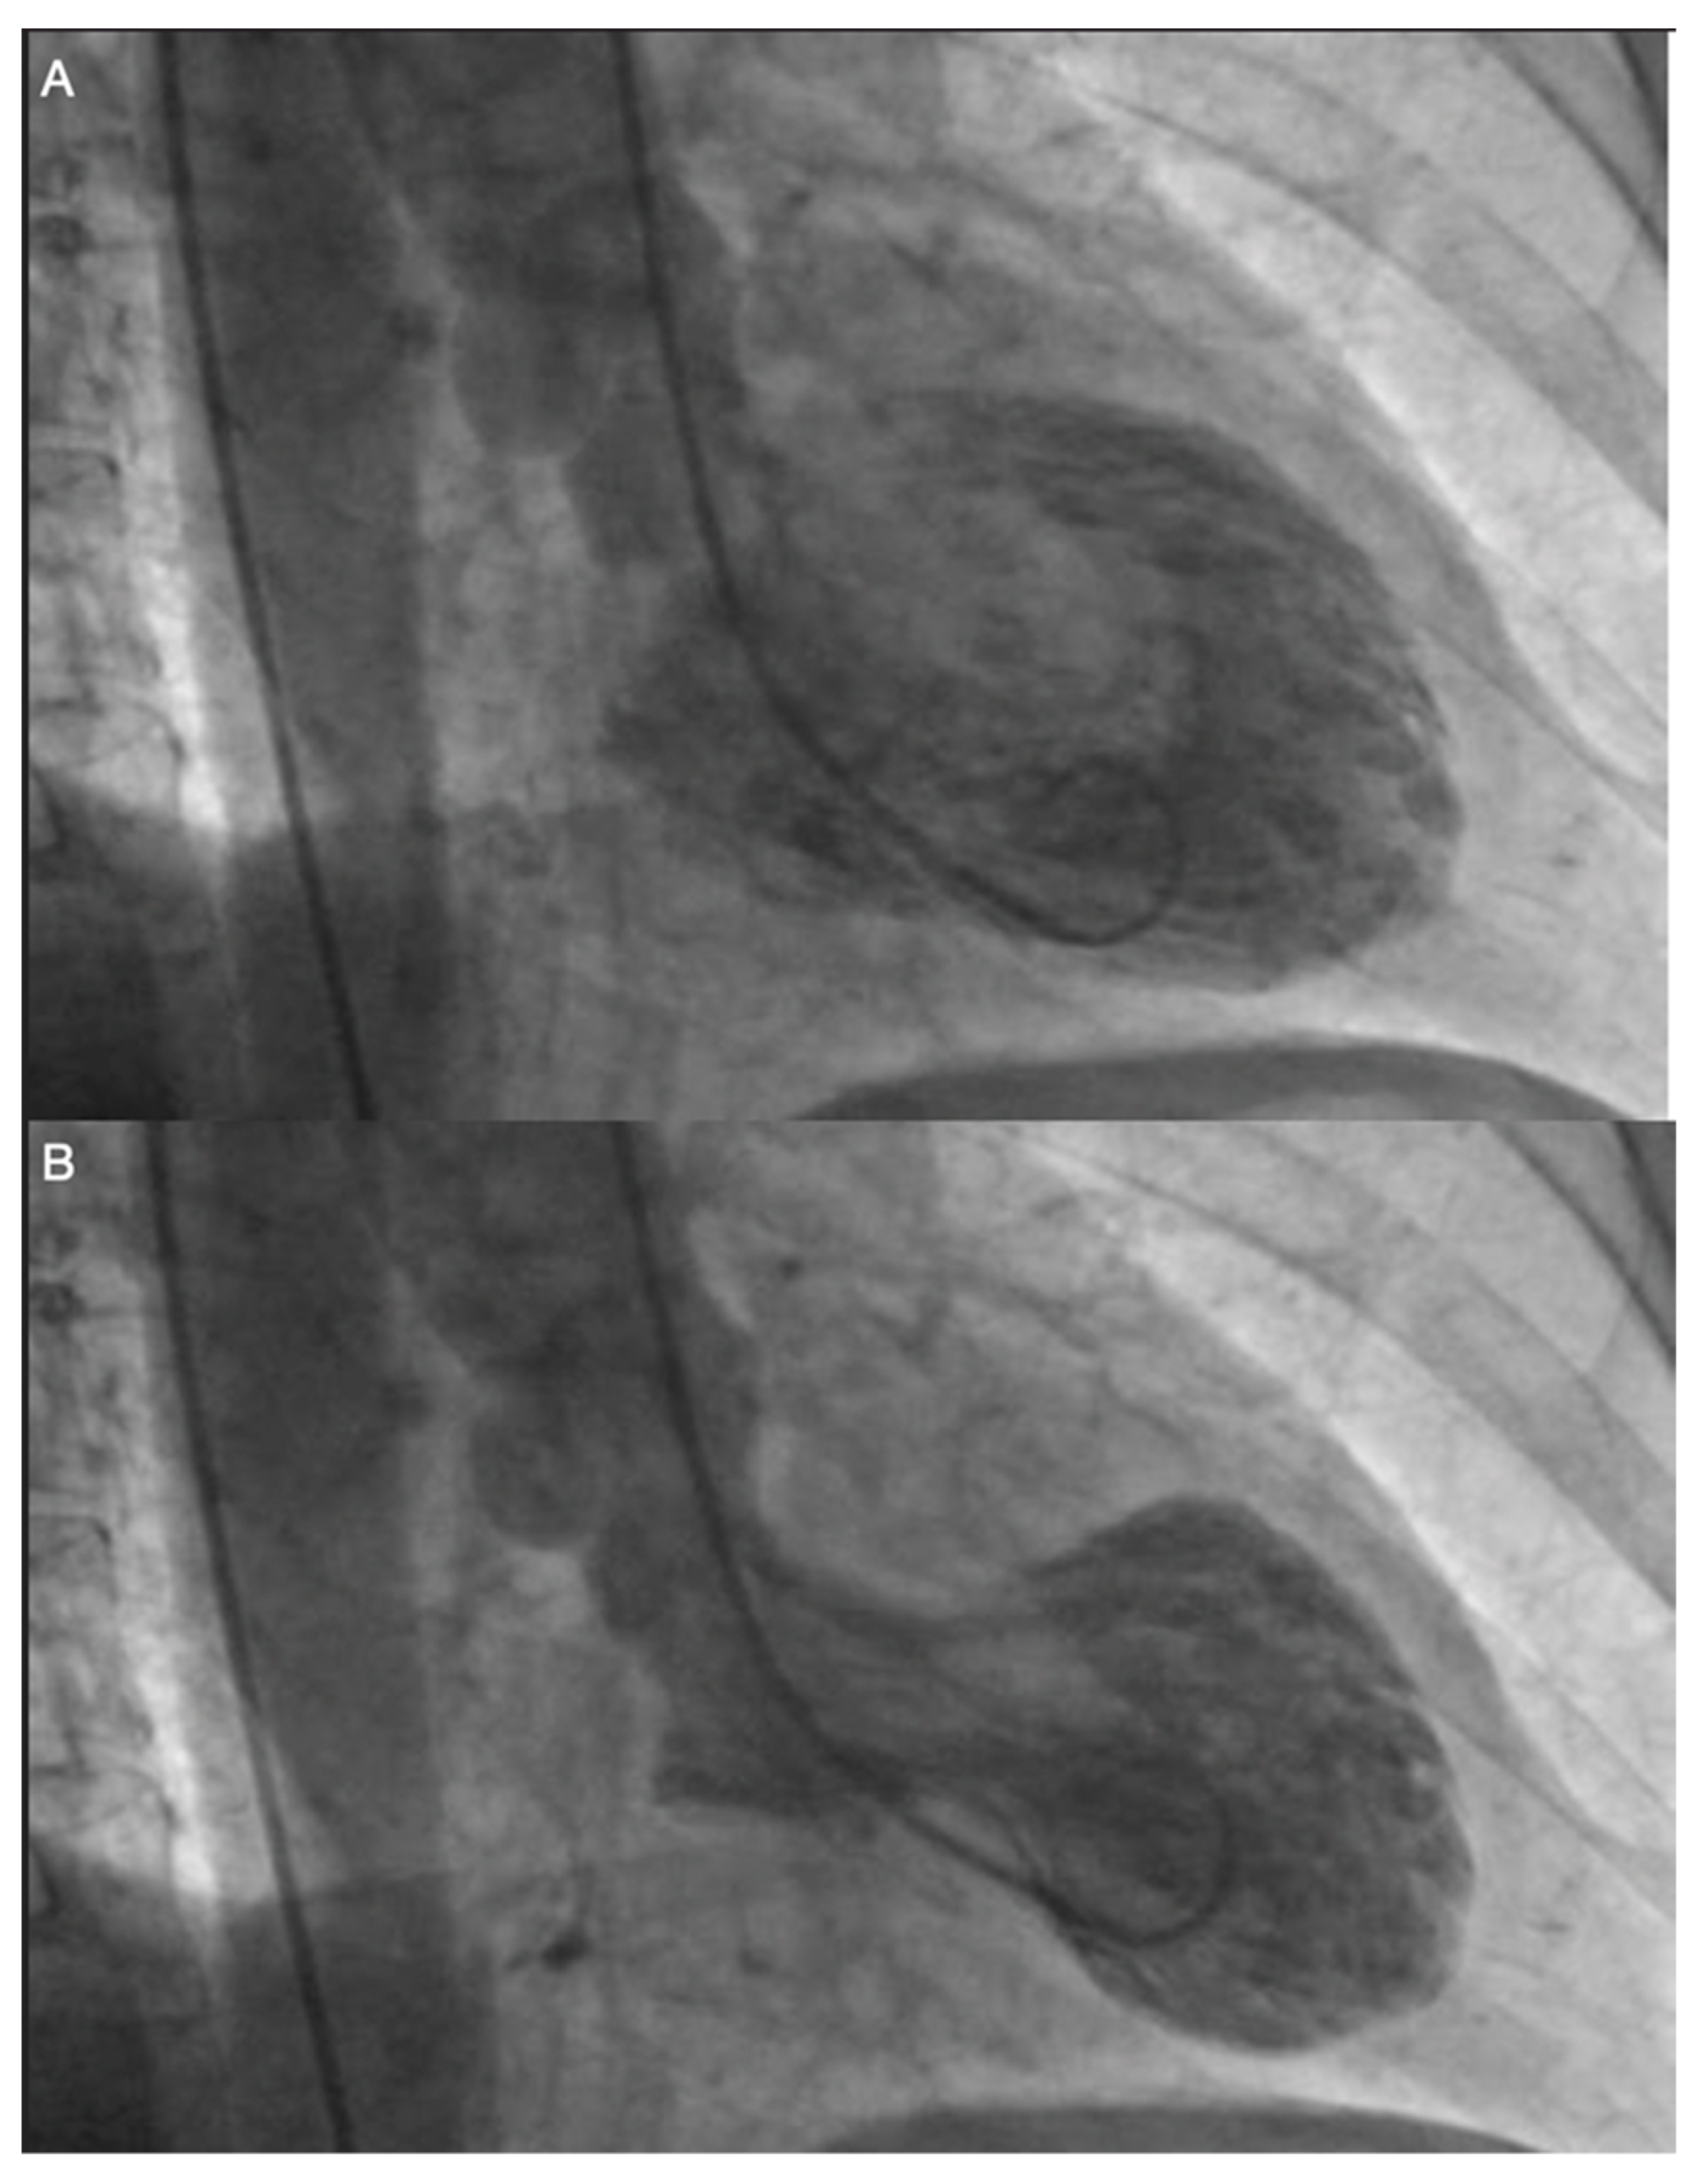

- Opolski, G.; Kochanowski, J.; Torbicki, A.; Scisło, P.; Kowalik, R.; Piotrowska-Kownacka, D.; Zarebiński, M.; Pruszczyk, P.; Kalarus, Z. The recurrence after ten years—“Mother in-law variant” of tako-tsubo syndrome. Kardiol. Pol. 2010, 68, 557–561. [Google Scholar]

- Opolski, G.; Budnik, M.; Kochanowski, J.; Kowalik, R.; Piatkowski, R.; Kochman, J. Four episodes of takotsubo cardiomyopathy in one patient. Int. J. Cardiol. 2016, 203, 53–54. [Google Scholar] [CrossRef]